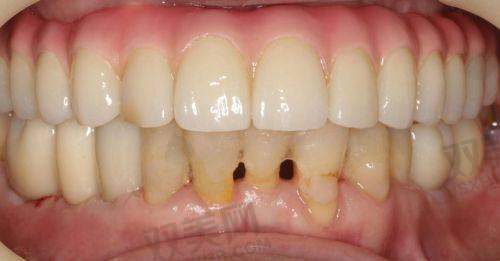

4. 口腔修复:包括烤瓷牙、全瓷牙、活动假牙等修复方式,为患者修复牙齿的形态和功能。